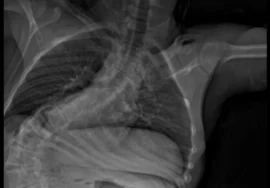

يُعد اعوجاج العمود الفقري (الجنف) من أكثر المشكلات شيوعًا بين الأطفال والمراهقين، ويُعتبر العلاج بالحزام الطبي (TLSO) أحد أهم الطرق غير الجراحية للسيطرة على الانحناء أثناء النمو. لكن مع اختلاف الحالات بين انحناء صدري وآخر قطني، يطرح الأهل سؤالًا مهمًا:

هدفت الدراسة إلى معرفة ما إذا كان موقع الانحناء وشكله (المورفولوجية) يؤثران على نتائج العلاج بالحزام، حتى عندما تكون درجة الانحناء متقاربة عند المرضى في البداية.

قام الباحثون بمتابعة 168 مريضًا مراهقًا يعانون من اعوجاج العمود الفقري مجهول السبب (AIS).

كانت زوايا الانحناء لديهم تتراوح بين 25 و45 درجة، وجميعهم في مراحل مبكرة من النضج العظمي (Risser من 0 إلى 2).

ثم تم تصنيف الانحناءات باستخدام نظام Lenke المعدل (mLenke)، وهو من أكثر الأنظمة دقة في تحديد نوع وشكل الانحناء.